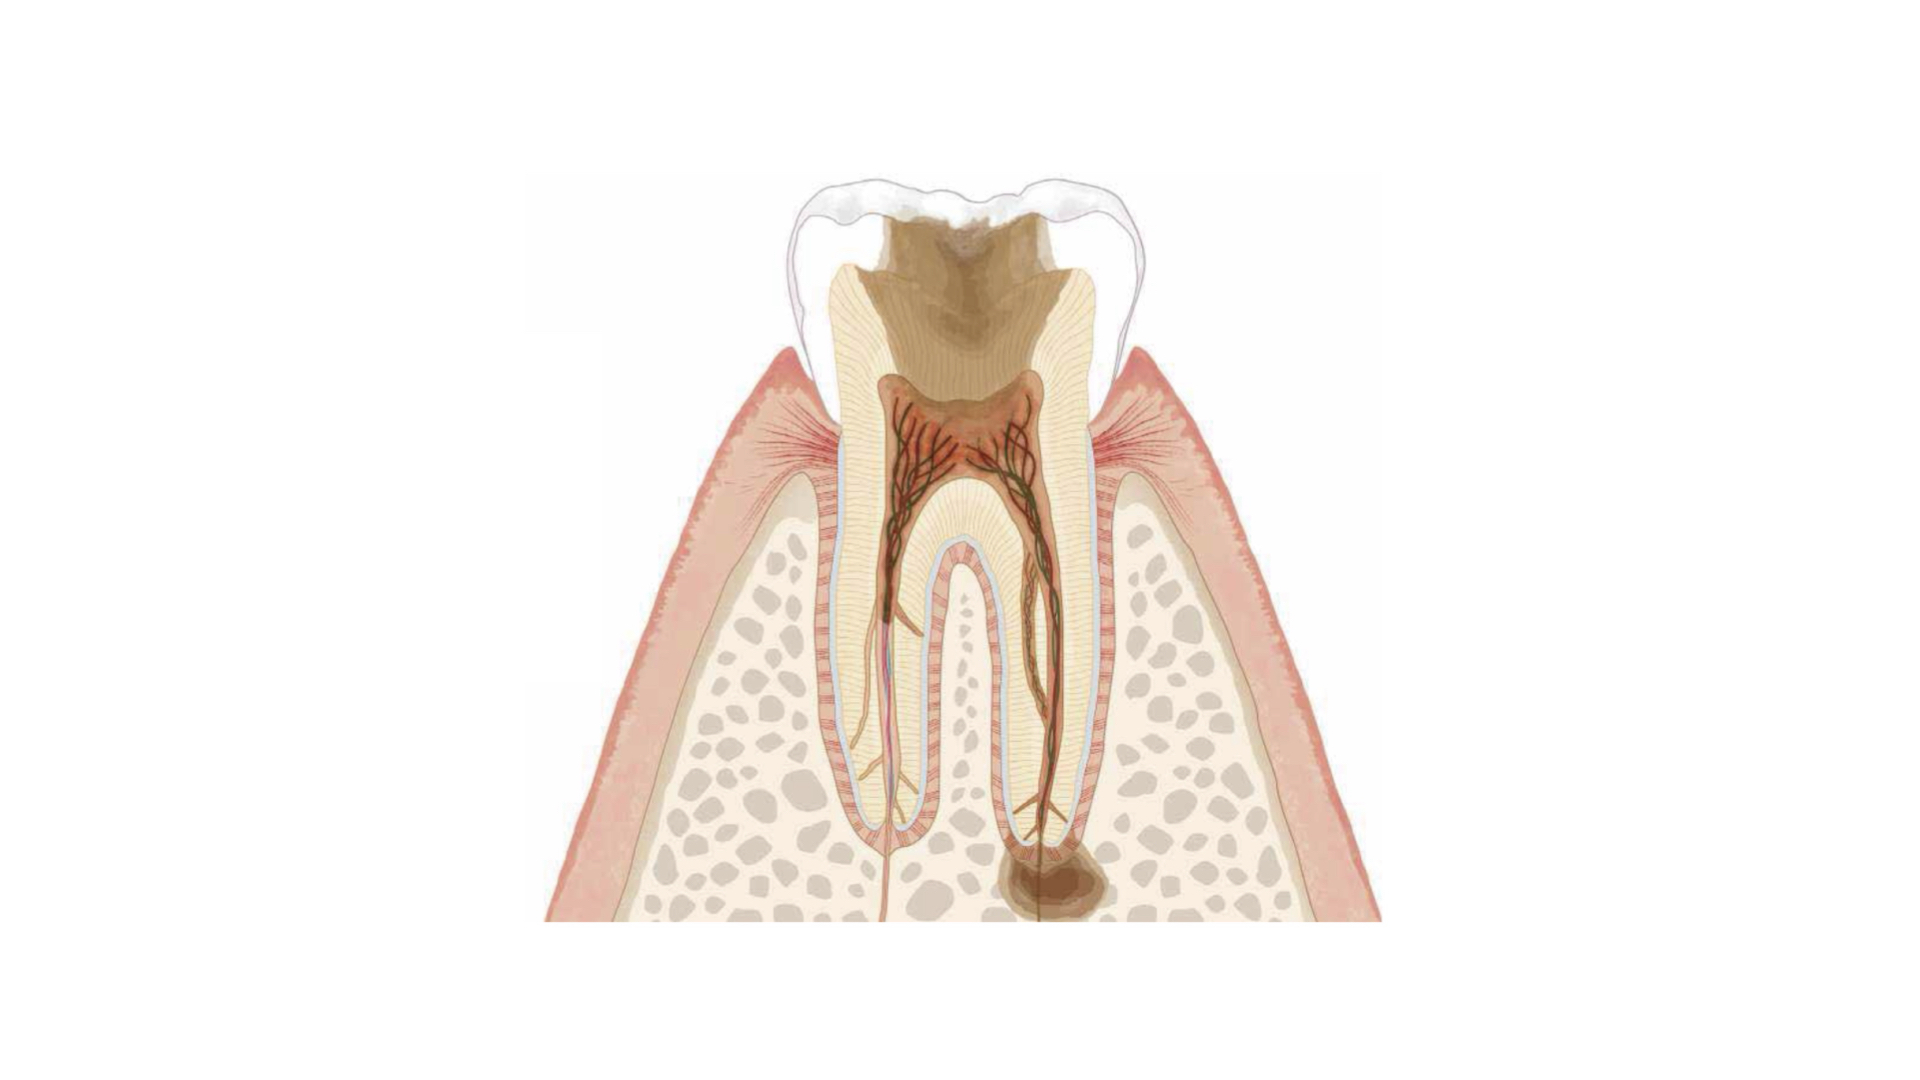

根の治療とは

歯の神経は、細い管の中に血管や神経繊維などが詰まった組織で迷路のような複雑な構造をしています。細い管を清掃して、お薬を緊密に詰めるのが根の治療(根管治療)です。